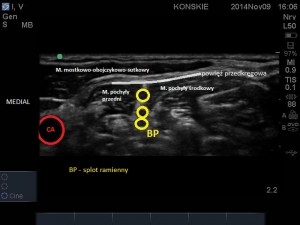

W celu uwidocznienia splotu w okolicy pomiędzy mięśniami pochyłymi, liniową głowicę USG przykładamy w obrębie trójkąta bocznego szyi, starając się uwidocznić tętnicę, żyłę szyjną wewnętrzną oraz zarys mięśnia mostkowo-obojczykowo-sutkowego. Po uwidocznieniu naczyń szyjnych przesuwamy głowicę w kierunku grzbietowym, poszukując mięśni międzypochyłych: przedniego i środkowego, pomiędzy którymi znajdują się hipoechogeniczne pnie splotu (najczęściej 3). W celu optymalizacji obrazu konieczne jest dobranie odpowiedniego kąta skanowania tak aby czoło głowicy znajdowało się prostopadle do struktur nerwowych .

- Sonoanatomi splotu ramiennego w szczelinie międzypochyłej

- Anatomia nerwu przeponowego, BP – splot ramienny

W obrazie ultrasonograficznym możemy także odnaleźć powierzchownie położoną blaszkę przedkręgową powięzi szyi (hiperechogeniczna linijna struktura), którą przykryty jest splot, zarys mięśnia mostkowo-obojczykowo-sutkowego a także głębsze struktury takie jak tętnica kręgowa i wyrostki poprzeczne kręgów szyjnych. W bezpośrednim sąsiedztwie splotu, na przedniej powierzchni mięśnia pochyłego przedniego, tuż pod blaszką przedkręgową położony jest nerw przeponowy. Takie implikacje anatomiczne sprawiają, iż jednostronna blokada nerwu przeponowego jest praktycznie nieunikniona przy wykonywaniu blokady splotu ramiennego z dostępu pomiędzy mięśniami pochyłymi z wykorzystaniem standardowych dawek LMZ (Film poniżej).